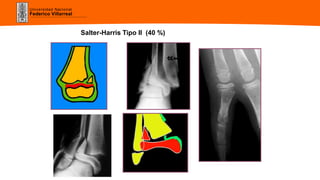

Salter-Harris Tipo II (40 %)

Salter-Harris Tipo II